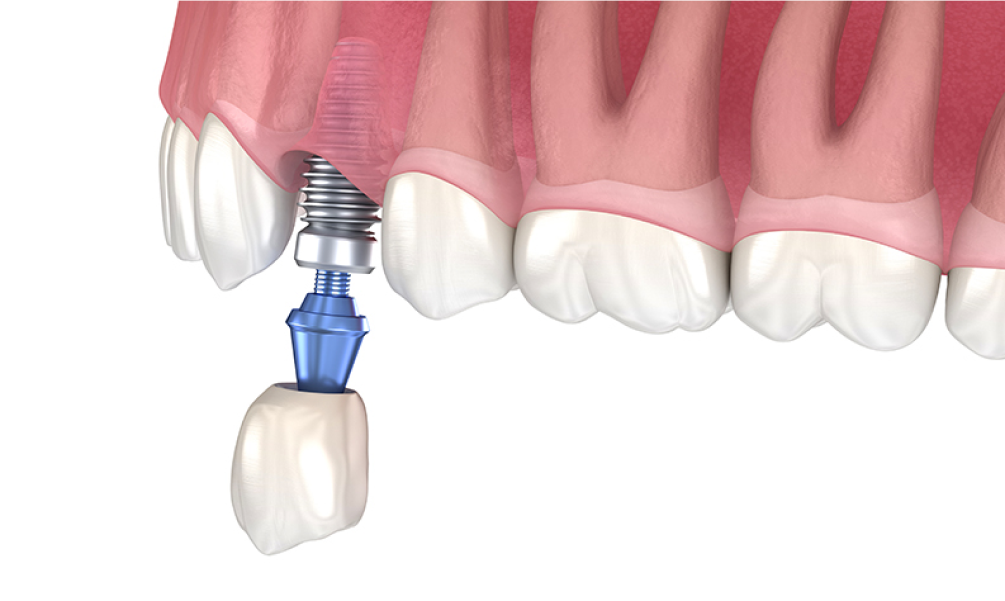

STEP 03 임플란트 치근 식립

잇몸뼈가 완전히 융합하여 자리 잡은 것을 확인한 뒤 임플란트의 인공치근을 식립합니다.

• 보철물 결합

STEP 04 보철물 결합, 수술 완료

임플란트의 인공치근이 단단하게 고정된 후에 환자에게 맞춤 제작한 보철물을 상부에 결합시켜 수술이 완료됩니다.